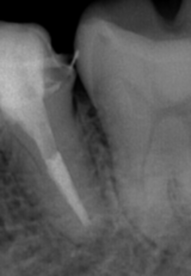

すき間なく緊密に根管充填されている

再感染リスクを抑える垂直加圧方式で充填しています(すき間が生じにくい)

根管治療は1回で終了。